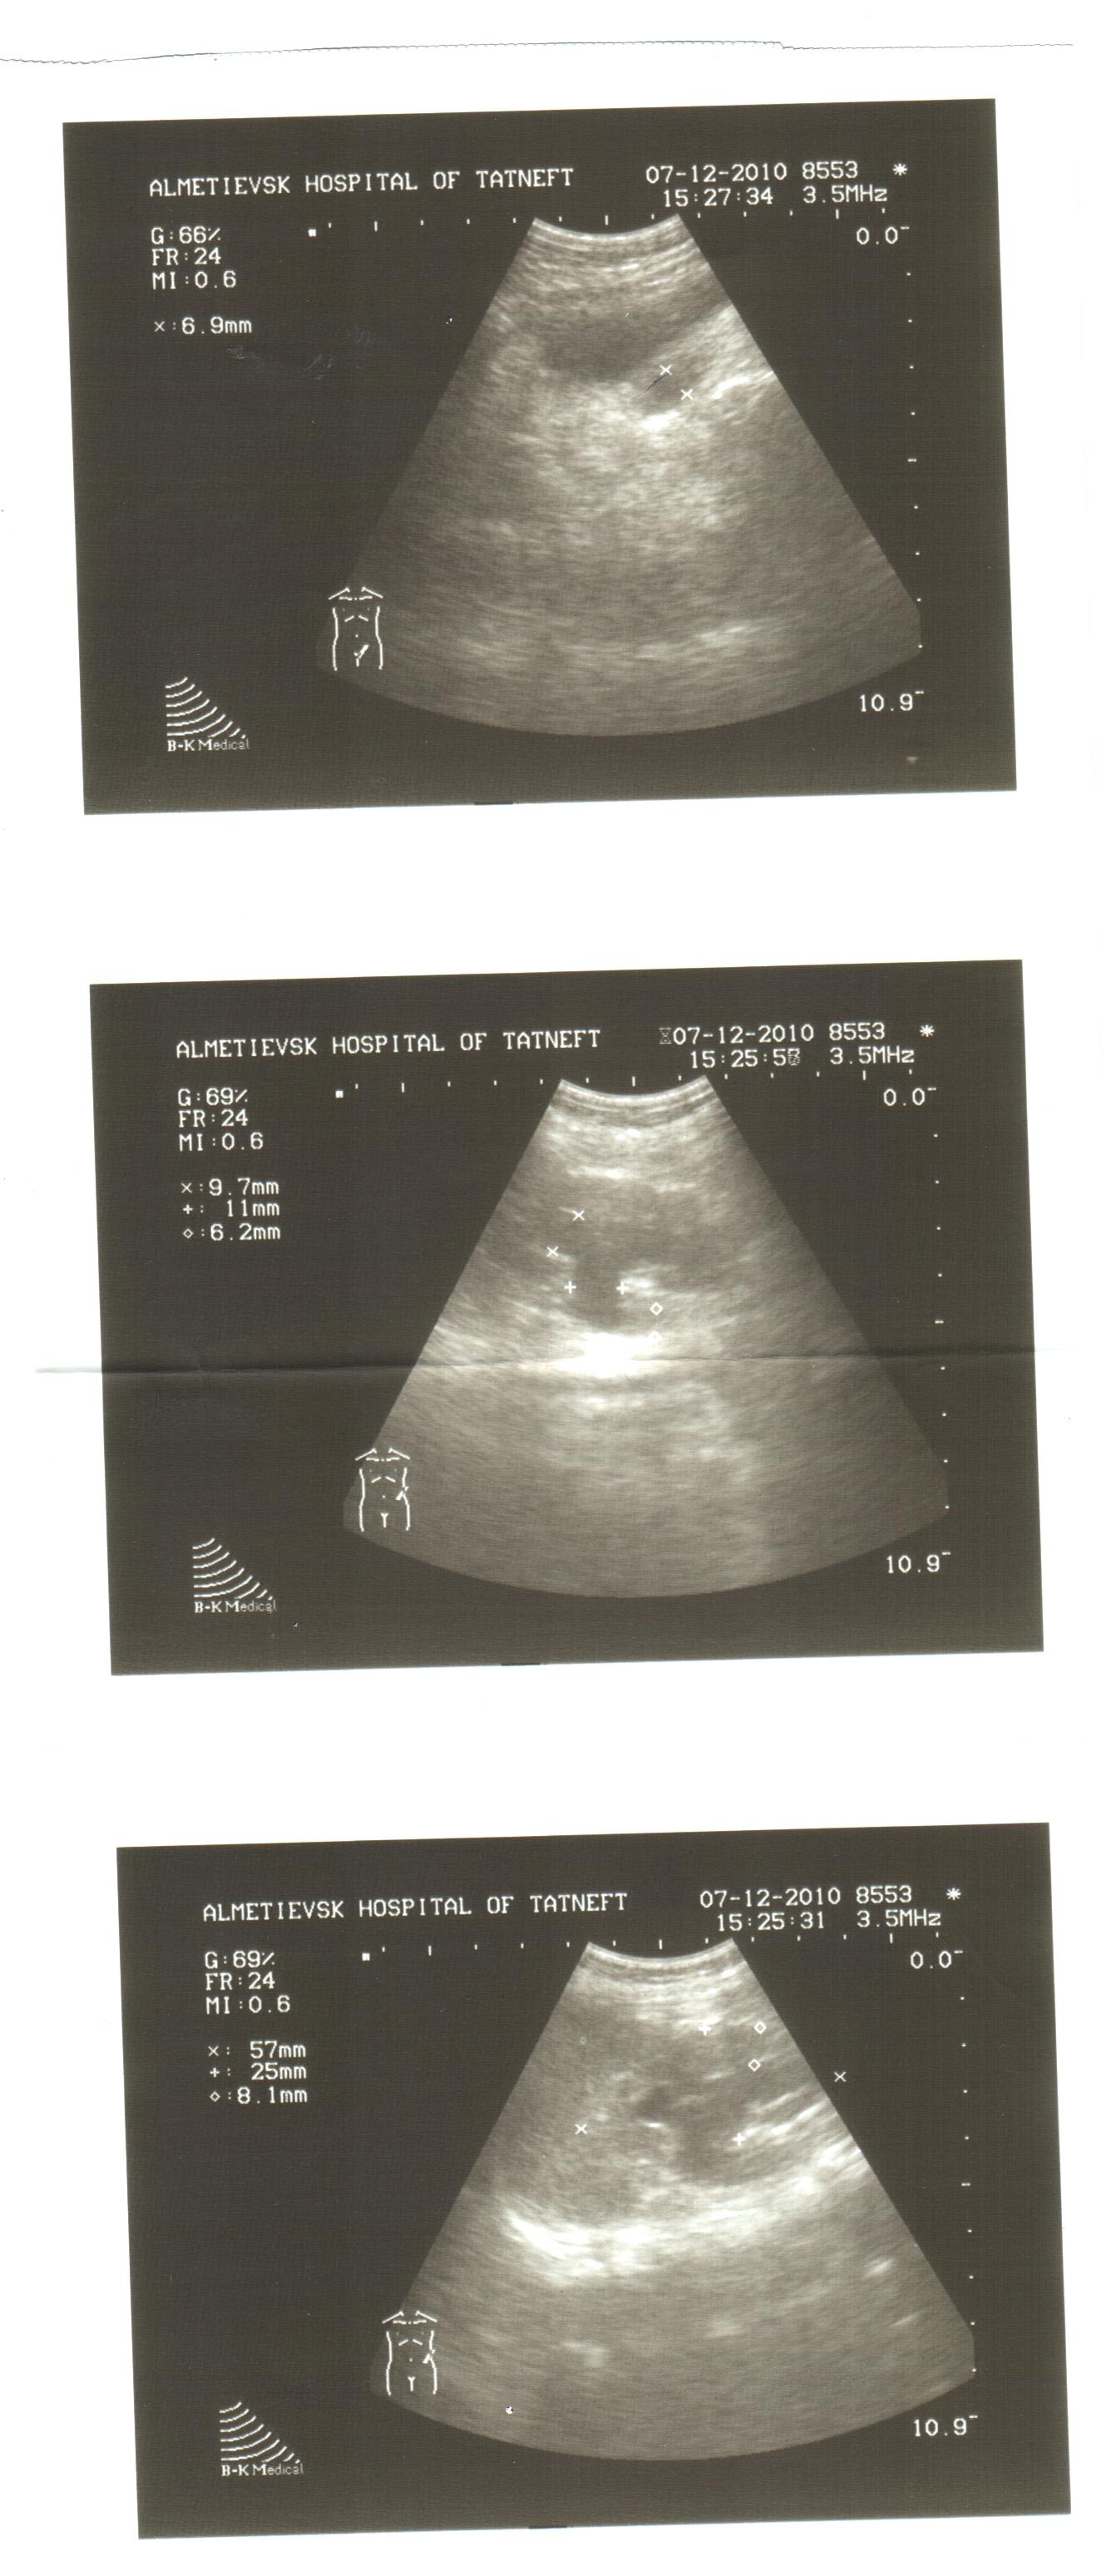

Здравствуйте! В 3 месяца ребенку поставили диагноз уретрогидронефроз 2-3 ст. слева. Ездили в ДРКБ в Казани, вот данные УЗИ:

Левая почка: 66х34 мм,

форма обычная,

паренхима(верхний полюс,область ворот, нижний полюс)-7,5 мм,

объем лоханки 5,6 см в кубе,

D чашечек 9 мм,

мочеточник дилатирован в пиелоуретральном отделе 9,8 мм, средней трети 9,3 мм, верхней трети 8,4 мм, дист отд - 11,3 мм.

правая почка: 52х26 мм,

ЧЛС без особенностей.

В 5 месяцев снова поехали на консультацию к тому же урологу(он сам проводит УЗИ). Он поставил диагноз стриктура н/з левого мочеточника, гидронефроз 2 ст слева. На УЗИ (прикрепленный файл) пиелокаликоэктазия слева (чашечки 9 мм, лоханка 11 мм), сказал что заужено в месте, где мочеточник соединяется с мочевым пузырем(мочевой пузырь был полным).